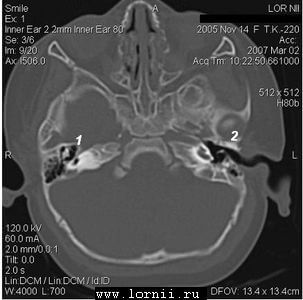

КТ височных костей выявила наличие двухсторонней аномалии развития улитки в виде неполного разделения I типа (табл. 4). При этом данное утверждение верно как для левого, так и для правого уха, несмотря на различную, на первый взгляд, картину (рис.1).